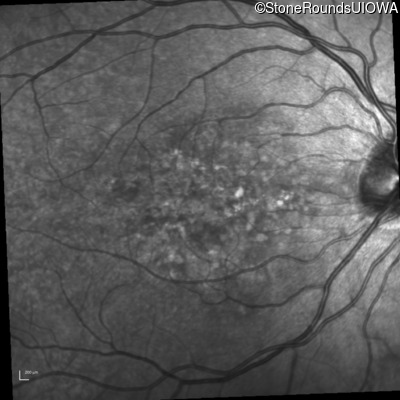

Infrared Fundus Photograph - Right - 20/25 -1 sc

Exemplar